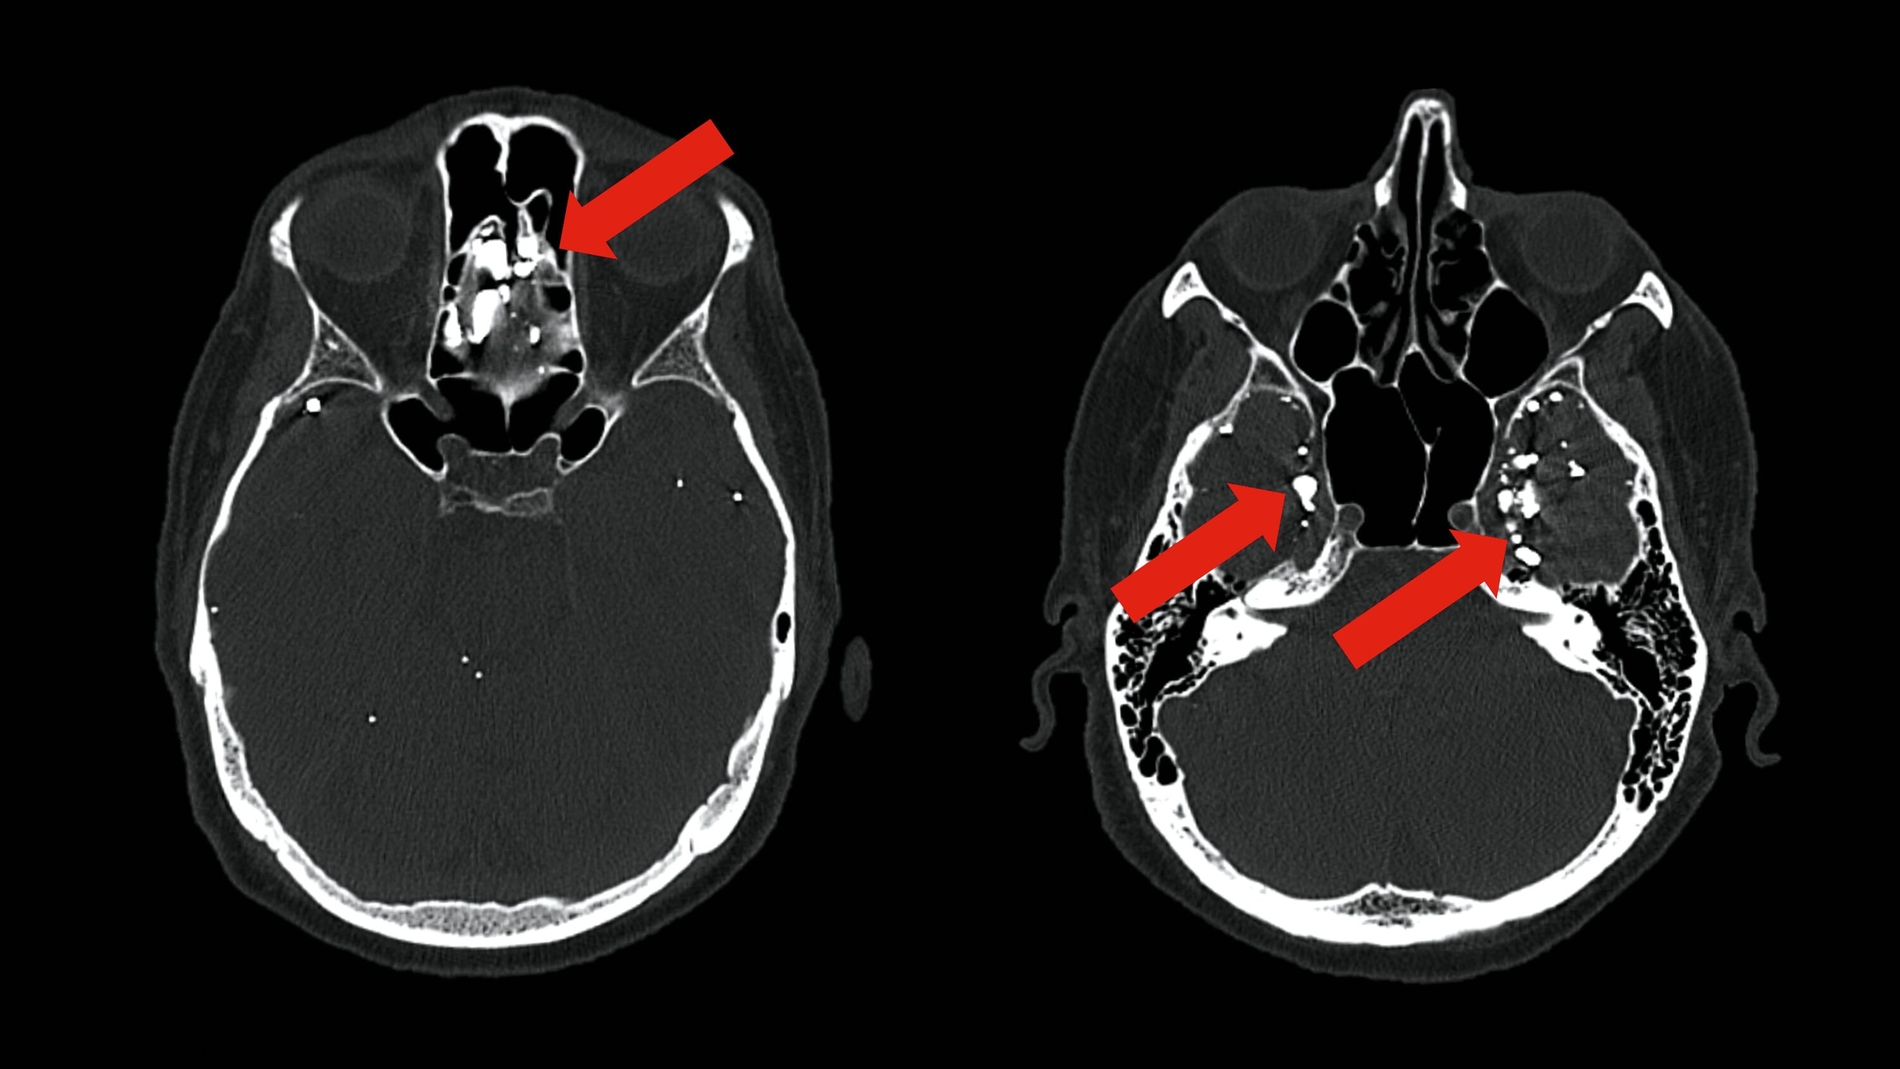

Das CT bestätigte multiple, teils rundliche, teils längliche, hoch röntgendichte Ablagerungen innerhalb der Liquorräume, vor allem supratentoriell und in den frontobasalen Abschnitten. Es zeigten sich keine Hinweise auf eine Liquorzirkulationsstörung, keine Raumforderungen, keine Mittellinienverlagerung und ein insgesamt unauffälliger Sella- und retrobulbärer Befund. Die basalen Zisternen waren frei. Die knöchernen Strukturen, einschließlich der Mastoidzellen, wiesen keine pathologischen Veränderungen auf.

Die beschriebenen Ablagerungen entsprachen dem röntgenologischen Eindruck aus dem OPG und warfen die Frage nach ihrer Genese auf. Eine mögliche differenzialdiagnostische Überlegung waren Ablagerungen des mittlerweile sehr selten verwendeten, öligen Kontrastmittels Lipiodol.